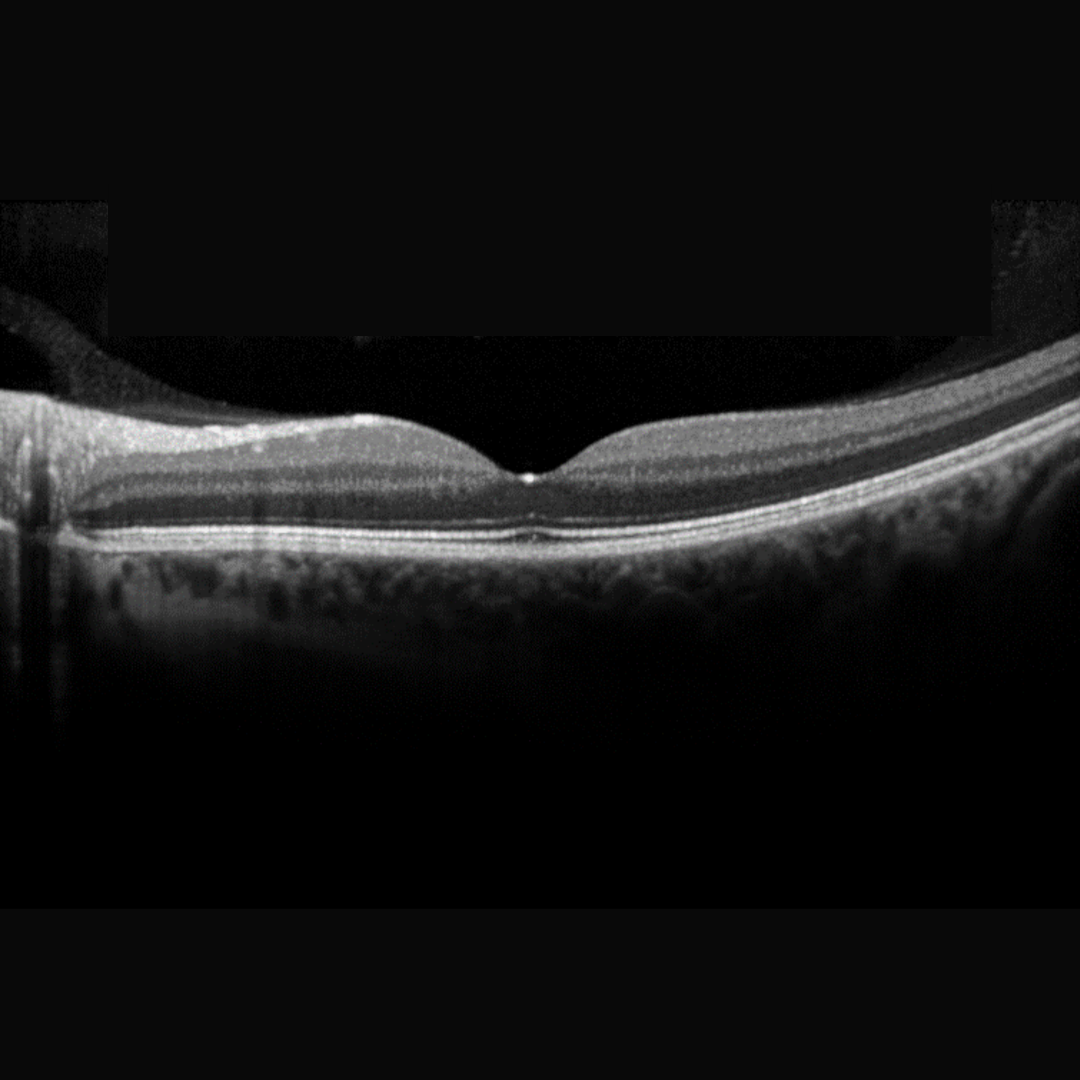

Normal Vitreoretinal Attachments

Vitreous adhesion to the retinal internal limiting membrane (ILM) is strongest at the vitreous base and margins of the optic disc. Other attachments exist at the macula and posterior lens surface and there are weak attachments along the superficial retinal vessels.